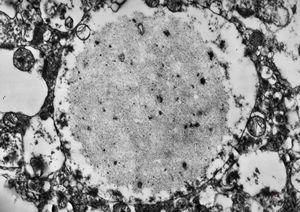

F,50y. | progressive multifocal leukoencephalopathy- viral particles in a glial cell